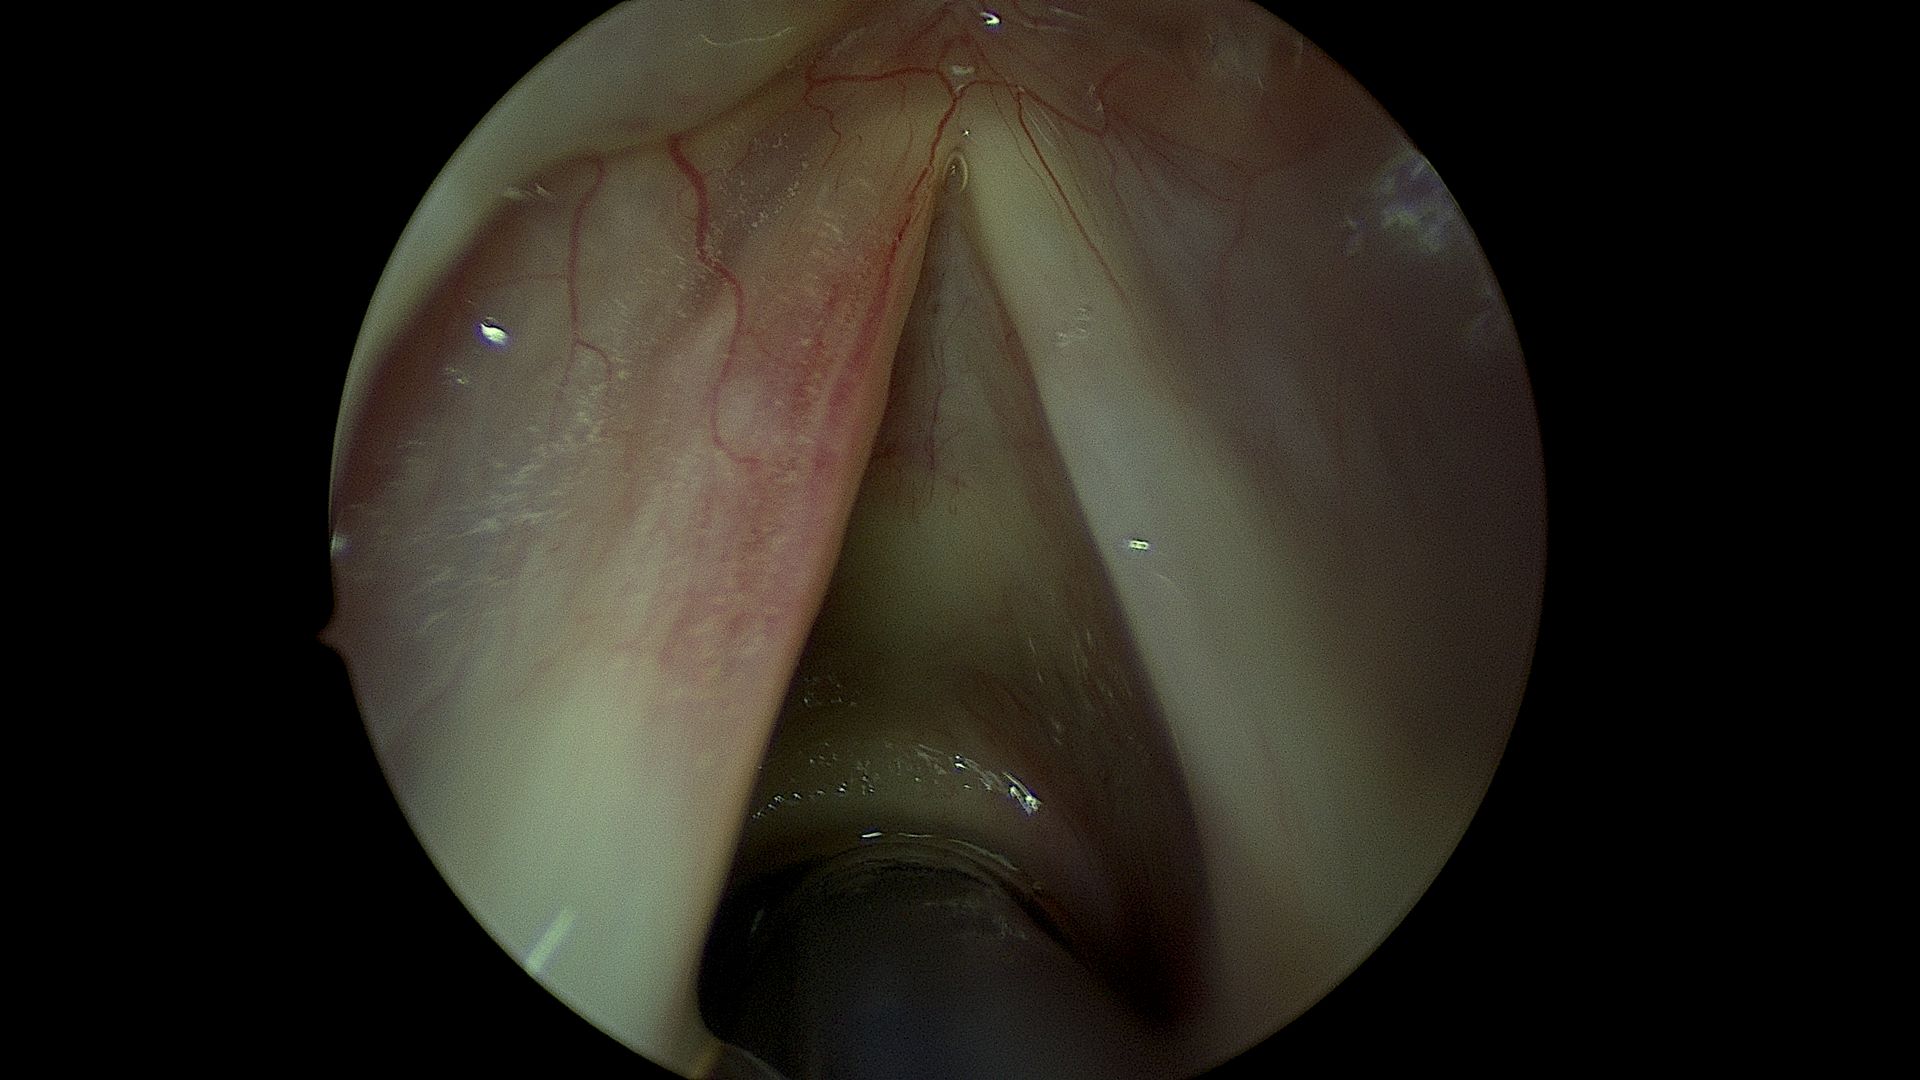

Post Microflap removal

After: microflap surgery for a cyst